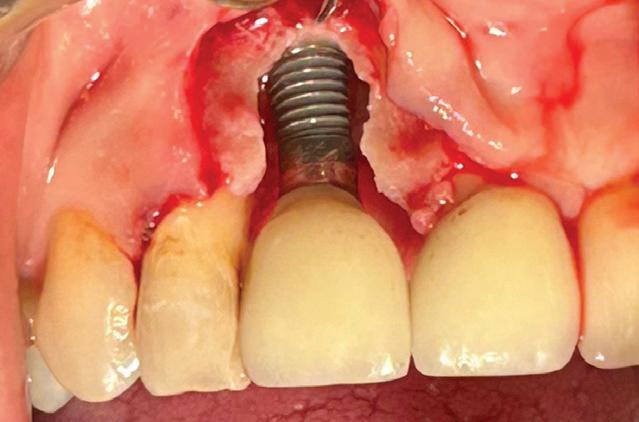

Each year, millions of people get dental implants as a longterm, natural-looking fix for missing teeth. But traditional implants don’t fully mimic real teeth.

Researchers from Tufts University School of Dental Medicine and Tufts University School of Medicine recently described a new approach to dental implants that could better replicate how natural teeth feel and function. Their study, published in Scientific Reports, shows early success with both a “smart” implant and a new gentler surgical technique in rodents.

“Natural teeth connect to the jawbone through soft tissue rich in nerves, which help sense pressure and texture and guide how we chew and speak. Implants lack that sensory feedback,” said Jake Jinkun Chen, DI09, a professor of periodontology and director of the Division of Oral Biology at the School of Dental Medicine and the senior author on the study.

Traditional dental implants use a titanium post that fuses directly to the jawbone to support a ceramic crown, and the surgery often cuts or damages nearby nerves. To tie these inert pieces of metal into the body’s sensory system, the Tufts team developed an implant wrapped in an innovative biodegradable coating. This coating contains stem cells and a special protein that helps them multiply and turn into nerve tissue. As the coating dissolves during the healing process, it releases the stem cells and protein, fueling the growth of new nerve tissue around the implant.

The coating also contains tiny, rubbery particles that act like memory foam. Compressed so that the implant is smaller than the missing tooth when it’s first inserted, these nanofibers gently expand once in place until the implant snugly fits the socket. This allows for a new minimally invasive procedure that preserves existing nerve endings in the tissue around the implant.